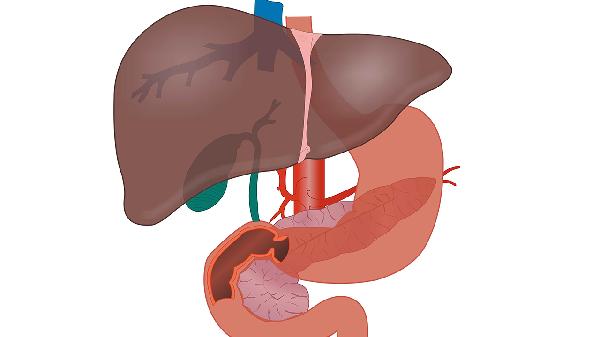

攜帶者只是體內有病毒,但肝臟功能正常,不需要治療。而乙肝患者已經出現肝功能異常,需要醫療干預。就像家裏來了不速之客,一個只是賴著不走,另一個已經開始拆房子了。

規範的隨訪治療下,只有不到10%的慢性乙肝會發展為肝硬化,其中又只有部分會惡變。現在醫療條件下,乙肝完全可以做到與癌”絕緣”。